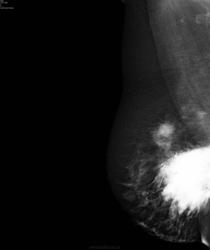

Обратилась дама. Жалоб нет. Чего бы ей написать?

Это коммерсанты в 90-годы парафин ввели или силикон.